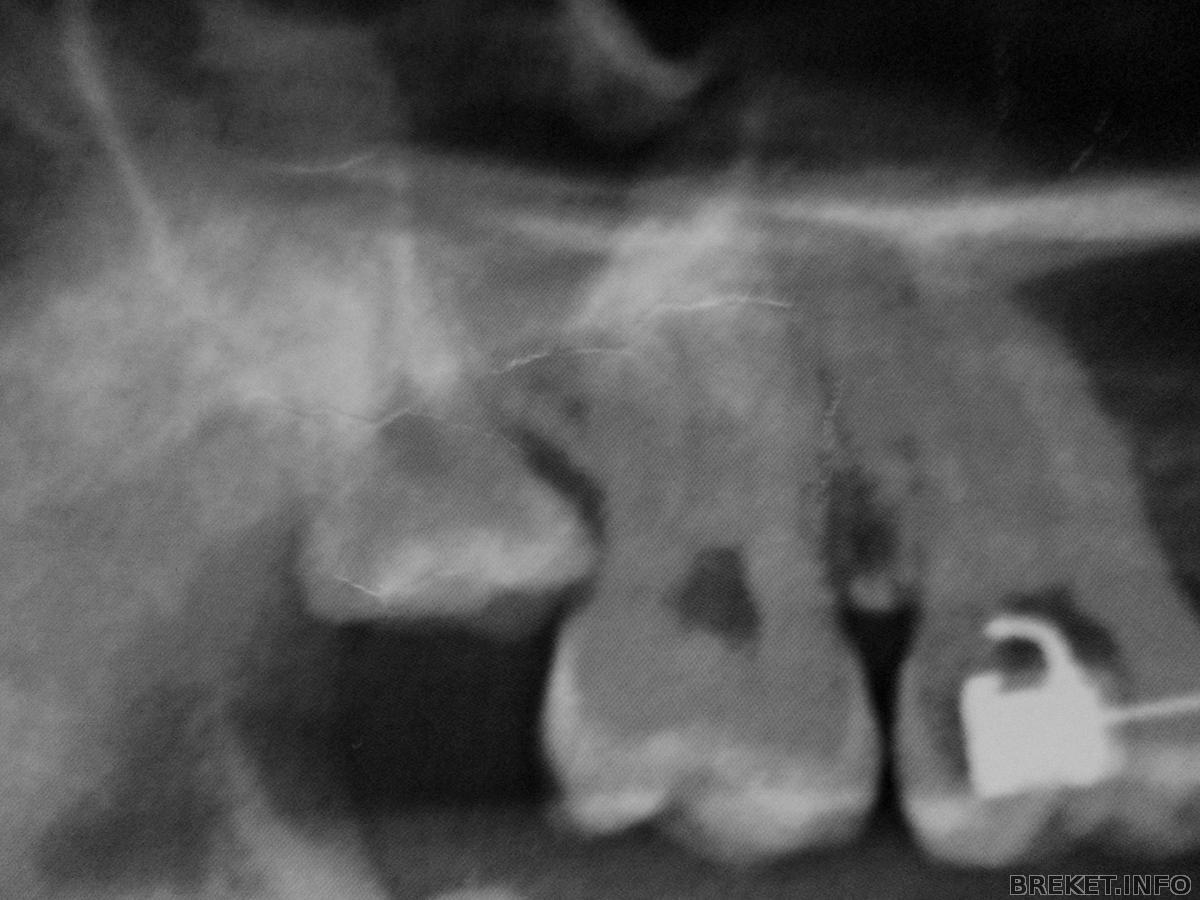

У меня на фото http://breket.info/images/image1073830261 левая нижняя( в жизни правая) ее убрали. Другую нижнюю тоже удаляю в скором времени. Орт заставил( С др стороны ортодонту виднее. У меня капец как упираются 8 в 7. Мне по большей части из -за правой ( на фото) удалить сказали, если бы не она может и пронесло бы